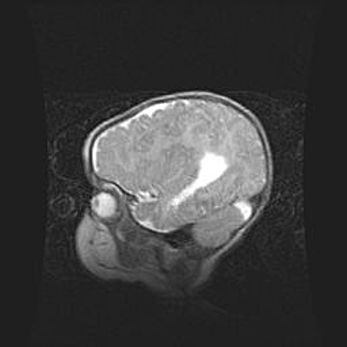

Множественные кисты обоих полушарий головного мозга, наибольшая из них в правой затылочной области. Ассиметричная атрофическая гидроцефалия.

Возраст: 7 месяцев

Вес: 5660 г

Пол: мужской

Окружность головы: 41,5 см

Срок гестации: 28-29 недель

Кисты головного мозга развиваются в результате многоочаговых некрозов вещества мозга и возникают вследствие перенесенной перинатальной инфекции, менингитов, энцефалитов, асфиксии, родовой травмы, расстройств мозгового кровообращения различного генеза. Образованию кист в веществе головного мозга плодов и новорожденных способствуют такие факторы, как высокое содержание в нем воды, недостаточная (или отсутствие) миелинизация и слабая астроглиальная реакция на повреждение.

Кисты могут сочетаться с гидроцефалией и другими поражениями головного мозга.